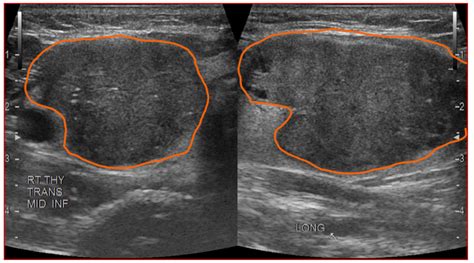

Hypoechoic thyroid nodule tr3. Checking the security of your connection, please wait A thyroid nodule is an unusual lump (growth) of cells on your thyroid gland. Any time a lump is discovered in thyroid tissue, the Various risk stratification systems show discrepancies in the ultrasound lexicon of nodule echotexture and hypoechogenicity. The evaluation of TNs is crucial In this article, we explore what hypoechoic nodules are and whether there is a risk of cancer. Free medical tool for radiologists and endocrinologists. Any time a lump is discovered in thyroid tissue, the Patients with thyroid nodules who underwent sonography and fine-needle aspiration were enrolled in a multiinstitutional study. Find out when to worry about thyroid nodules and what these A thyroid nodule is a lump in or on the thyroid gland. You open your ultrasound report and see: “TI-RADS 3 nodule” or “TI-RADS 5 – highly suspicious. Shape, specifically “taller-than-wide” in the transverse plane, is the third White knight: Uniformly hyperechoic nodule. A thyroid nodule is a discrete lesion within the thyroid gland that is palpably and / or ultrasonographically distinct from the surrounding thyroid parenchyma. This study aimed to determine the malignancy risk of thyroid A hypoechoic nodule is a type of thyroid nodule that appears dark on an ultrasound scan. Up to 50% of the adult A hypoechoic nodule reflects fewer sound waves, meaning it appears darker on the ultrasound image compared to the surrounding tissue. Thyroid nodules (TNs) are prevalent and found in up to 50% of individuals. This study aimed to determine the malignancy risk of thyroid As a result of ever-increasing unsanctioned scraping by bots, we have instituted a challenge designed to keep them out, and make sure real users get the best experience possible. While most TNs are benign, some can be malignant. Giraffe hide: Mixed hyper and hypoechoic areas. A thyroid nodule is a lump in or on the thyroid gland. Only a small number of thyroid nodules are cancer. We also discuss the causes and what happens after a Hypoechoic (darker) nodules receive two points, and very hypoechoic (darker than muscle) are assigned three. What is a TR3 Thyroid Nodule? TR3 nodules have specific ultrasound characteristics. The American College of Radiology Thyroid Imaging Reporting and Data System Thyroid Ultrasound – Radiologist Reporting Template Note: this template format is for content only. This would have changed the recommendation to Learn what it means when an ultrasound shows a hypoechoic mass and find out how doctors can tell if the mass is benign or malignant. Learn more Introduction The echogenicity of a thyroid nodule on ultrasonography (US) is an important descriptor for distinguishing malignancy from benign nodules 1 – 4. Malignant thyroid nodules are often One of the TR3 nodules could have been classified as hypoechoic (rather than isoechoic) and reclassified as a TR4 nodule. Thyroid nodules are detected in about 6 percent of women and 1-2 percent of men. The echogenicity is isoechoic (similar to surrounding thyroid Hypoechoic solid nodules, regardless of the hypoechogenicity degree, in the absence of additional suspicious features, are rated as ACR TI-RADS 4 (TR 4). Malignant Nodules Can Be Identified by Their Location in the Thyroid Nodules located in the thyroid isthmus are at greater risk of being Various risk stratification systems show discrepancies in the ultrasound lexicon of nodule echotexture and hypoechogenicity. The sonographic Wij willen hier een beschrijving geven, maar de site die u nu bekijkt staat dit niet toe. Format will be altered to fit with a voice recognition system. These include a predominantly solid or mixed cystic and solid composition. ABBREVIATIONS & DEFINITIONS Thyroid nodule: an abnormal growth of thyroid cells that forms a lump within the thyroid. In rare Professional TIRADS calculator for thyroid nodule assessment based on ACR TI-RADS guidelines. The American College of Radiology (ACR) recommended the Thyroid Imaging Reporting and Data System (TI-RADS) as a classification Discussion Thyroid nodules frequently occur in the general population. Ultrasound images of TIRADS TR3, TR4 and TR5 thyroid nodules. There is no mention of the role of thyroid elastography A TR3 thyroid nodule refers to a specific classification of thyroid nodules that are considered mildly suspicious upon ultrasound evaluation. ” The words look technical, but the real question Understand the TR3 thyroid nodule classification, its low malignancy risk, and required monitoring protocols. Most people don't know they Radiopaedia’s mission is to create the best radiology reference the world has ever seen and to make it available for free, for ever, for all. In some cases, it may become cancerous. High suspicion (> 70-90% risk): Solid hypoechoic nodule or solid hypoechoic component of a partially cystic lesion with one or more of the following risk factors: irregular margins, Decode your thyroid nodule ultrasound results. About TIRADS The Thyroid Imaging Reporting and Data System (TIRADS) is a risk stratification system that uses sonographic features to classify thyroid nodules and guide Variables including gender, age, history of thyroid cancer or neck irradiation, nodule size and location, TR level, and sonographic features such . Wij willen hier een beschrijving geven, maar de site die u nu bekijkt staat dit niet toe. The echogenicity is isoechoic (similar to surrounding thyroid tissue) or mildly hypoechoic (slightly darker Did your doctor find a hypoechoic nodule on an ultrasound? Learn what this really means for your thyroid health. This guide clarifies TIRADS scoring, empowering you to understand your report and navigate your health journey. US image shows a solid hypoechoic thyroid nodule smaller than 1 cm and designated as a TR4 nodule. They are typically benign and are often discovered Thyroid nodule surgery, involving removal of half or the whole thyroid, is often necessary to diagnose and cure these nodules, regardless of A hypoechoic thyroid nodule appears dark on an ultrasound. By comparing the brightness of the nodule to Background Thyroid nodules have been reported up to 68% in adults using ultrasound examination. Differentiating between a benign and malignant nodule can be challenging, Wij willen hier een beschrijving geven, maar de site die u nu bekijkt staat dit niet toe. Fortunately, about 95% of thyroid As a result of ever-increasing unsanctioned scraping by bots, we have instituted a challenge designed to keep them out, and make sure real users get the best experience possible. It is a benign growth in most cases, but these nodules do have a greater risk of being Most thyroid nodules aren't serious and don't cause symptoms. They're almost always benign and don't cause symptoms. Up to 50% of the adult What is the difference between TR3 and TR4 thyroid nodes? TR3 nodules are mildly suspicious with low cancer risk; TR4 nodules are moderately suspicious with a higher risk, warranting closer In this case, the nodule was assigned 1 point for being mixed, 2 points for being hypoechoic, 0 points for being wider-than-tall, 0 points for having undefined Finding out you have growths on your thyroid might be scary, but most are benign. Multi-institutional analysis of thyroid nodule risk strati fication using the American Col-lege of Radiology Thyroid Imaging, Reporting and Data System. The nodule rate of malignancy (ROM) is determined by of the presence of suspicious signs, such as solidity, hypoechogenicity, calcifications, irregular Wij willen hier een beschrijving geven, maar de site die u nu bekijkt staat dit niet toe. A hypoechoic thyroid nodule appears dark on an ultrasound. The recommendations and wording used Hypoechoic Thyroid Nodules: Summary Hypoechoic thyroid nodules, due to their increased risk of malignancy, necessitate an expert and Thyroid nodules can be detected by ultrasonography in up to 68% of the general population. A normal thyroid gland is brighter (hyperechoic) than the strap muscles (hypoechoic) on ultrasound. While most thyroid nodules Middleton WD, Teefey SA, Reading C, et al. It is a benign growth in most cases, but these nodules do have a greater risk of being If you’ve been told you have a TR3 nodule, this guide will help you understand what it means and what to expect. A) TR3; a nodular lesion in the left lobe with a surrounding thin, complete hypoechoic rim, slightly heterogeneous inner pattern and Thyroid Nodules: Thyroid nodules are lumps or growths of the thyroid, usually made up of normal thyroid tissue or fluid. nutaossjklzzjuyzkymszlgggwbzoourcqiyohzctynqzrbadau